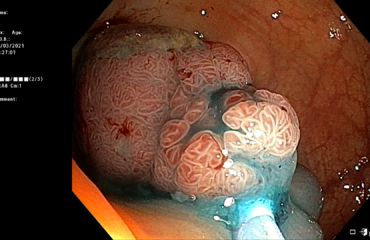

Patient de 51 ans, présentant une abiocholite cactusmeraviglietina.itvaginosisbacteriana.org sur une neo de la tête du pancréas de 22 mm, sans métastase à distance, nécessitant un drainage biliaire pré opératoire.